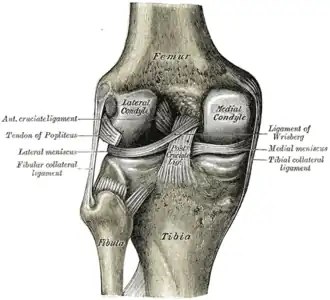

Left knee joint from behind, showing interior ligaments

Left knee joint from behind, showing interior ligaments -